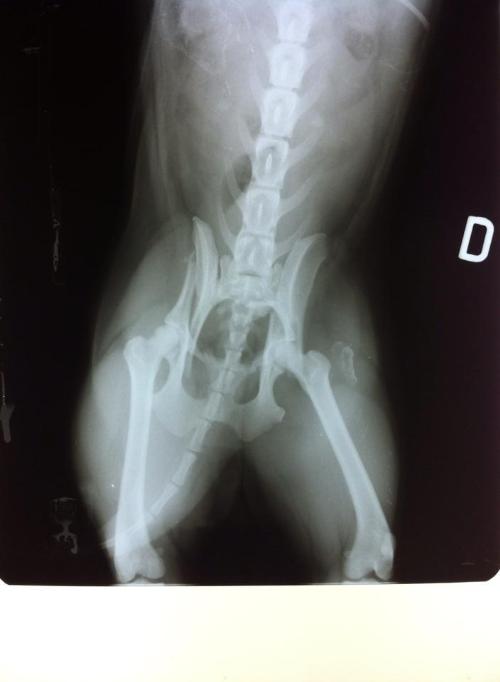

Gatto Frattura Bacino Clinicaveterinaria Org Forum Source: clinicaveterinaria.org

Cane Con Frattura Del Bacino Inserite Lastre Sul Ponte Il Veterinario Risponde Source: clinicaveterinaria.org

Ciao a tutti. Mariarosaria91 Buonasera stanotte hanno investito il mio gatto di un anno procurandogli una frattura del bacino. Rintracciato dai militari è stato denunciato. Ciao a tutte 11 anni fa a causa di un incidente stradale ho subito una frattura ileo ischio pubica in 4 punti. Della branca ischio pubica delle spine iliache antero-superiori e inferiori.

Iliaco ischio e pube che sono saldati insieme. Mariarosaria91 Buonasera stanotte hanno investito il mio gatto di un anno procurandogli una frattura del bacino. Frattura bacino pareri. Ho la fortuna di non dover fare riabilitazione perché non mi sono rotta unarticolazione. Ora mi chiedevoci saranno problemi per un parto naturaleLa mia gine mi ha detto che magari è meno elastico di un bacino normale ma che comunque visto che è anche il primo figlio non se ne parla di cesareo meno male.

Non sono qua per farmi fare la morale sono uscito da una frattura scomposta del bacino che mi ha tenuto fermo 2 mesi e mezzo per lavoro alle 3 di notte devo farmi questa 30ina di km per rientrare e sono qua per imparare quello che non ho mai imprato sulle bici in particolar modo le ebike. Entità e tipo della frattura si potranno capire solo dalla radiografia. Frattura del bacino 30 giorni a letto e dopo. Mariarosaria91 Buonasera stanotte hanno investito il mio gatto di un anno procurandogli una frattura del bacino. Eusebio clinica veterinaria asola clinica veterinaria mantova clinica veterinaria provincia di mantova clinica veterinaria cremona c.

Forum Ragazze Fuori di Seno SpazioUtenti. Ho la fortuna di non dover fare riabilitazione perché non mi sono rotta unarticolazione. Per ulteriori approfondimenti si può ascoltare la puntata del 24 aprile scorso della rurbica Sport e Salute a cura del Prof. Mariarosaria91 Buonasera stanotte hanno investito il mio gatto di un anno procurandogli una frattura del bacino. Qualche dolorino lo avverto ma se è vero che non.